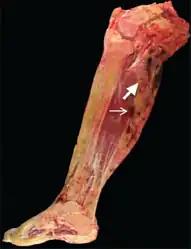

55-year-old female who initially presented with progressive right posterior calf pain now status post right leg amputation for malignant tenosynovial giant cell tumor. Gross pathology of the amputated right lower extremity reveals a heterogeneous tumor with cystic (thick arrow) and solid (thin arrow) components extending from the popliteal fossa to the mid-calf.